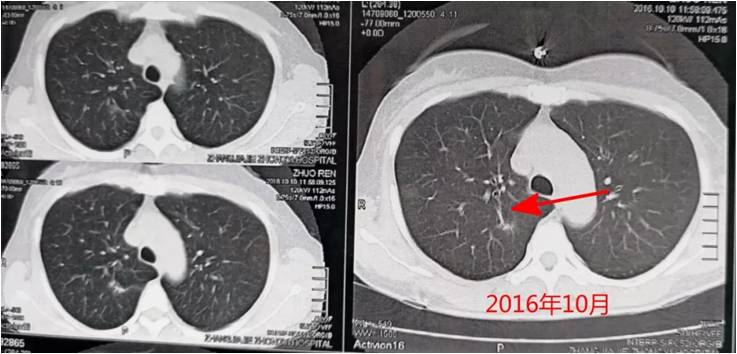

一年之后,右上肺結節進行性增大,如下圖:

從患者的CT片可以看出,右上肺的病灶明顯變大、變實。結合患者為中年女性,不能排除惡性病變的可能。故動員患者予以手術治療,患者接受了醫生建議。

手術之后,結節病理診斷為中分化肺腺癌,這是一起臨床常見的肺磨玻璃樣結節(GGO)病變病例。